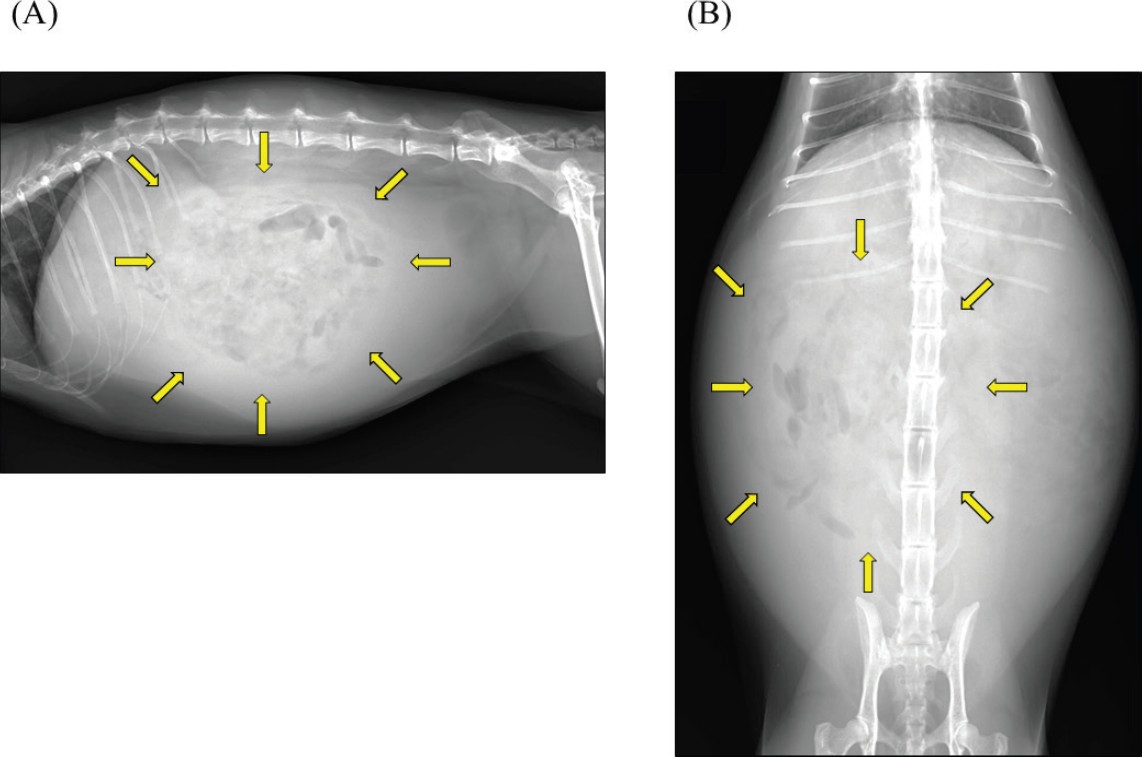

腹部超声发现严重腹水、小肠蠕动减弱、胰腺增大,腹膜不规则增厚并伴有多个结节(下图)。

↑ 腹部超声。整个腹部观察到严重腹水。(A)左上腹部观察到一个低回声不规则区域(箭头),被认为是增大的胰腺。(B)腹膜表现出不规则增厚,内部有散在的低回声结节形成(三角)。心脏超声未发现异常。